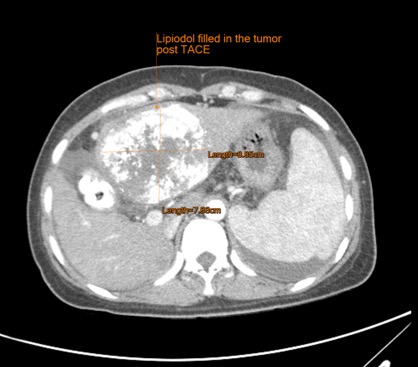

หลังทำ TACE แบบเร่งด่วน เลือดหยุด ผู้ป่วยมีความดันคงที่ และกลับบ้านได้

ภาพ CT หลังทำ 1 เดือน ก้อนมีขนาดเล็กลงไม่มาก แต่ยาที่ให้ร่วมกับสารที่อุดหลอดเลือดระดับปลาย (สีขาว ทั่วไปภายในก้อน) เข้าไปแทนที่ภายในก้อนมะเร็งเกือบทั่วทั้งก้อน